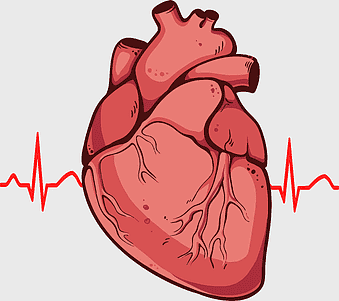

red heart anatomy, human heart drawing, cartoon heart illustration, love and biology, cardiovascular system diagram, medical art depiction, organ structure visualization -

human heart anatomy, cardiovascular system illustration, medical heart diagram, heart organ structure, human body organ visuals, anatomical heart drawing, heart health -

Heart Anatomy Diagram, human heart drawing, realistic heart illustration, cardiovascular system, medical illustration, organ structure, human anatomy study -

human heart anatomy, cardiac muscle illustration, circulatory system model, heart health visual, cardiovascular organ diagram, medical heart image, visceral structure depiction -

human heart diagram, cardiovascular system anatomy, blood vessel chart, free body diagram, circulatory system illustration, medical organ visualization, human anatomy study -

heart bear illustration, myocardial infarction symptoms, cardiovascular disease diagram, red blood cell flow, heart anatomy art, circulatory system model, thrombus medical image -